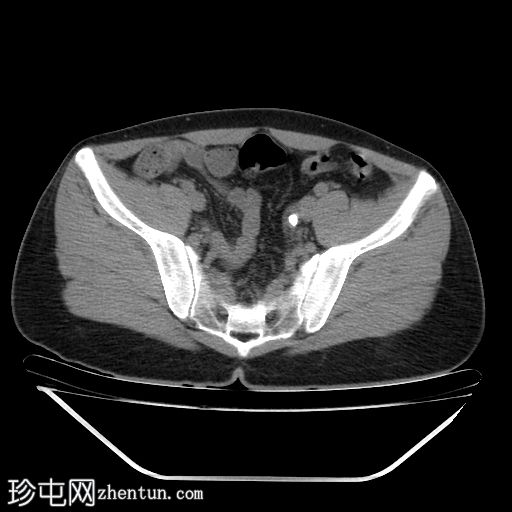

轴位

非增强CT

右肾上盏内可见多发微小结石。

左肾上盏内可见一枚孤立性微小结石。

左侧输尿管远端,距膀胱输尿管连接处(VUJ)近端约4 cm处,可见一枚边界清晰的结石,最大轴向直径约14mm,导致轻度左侧输尿管肾积水。

未见明显的肾周脂肪浸润。

未发现其他急性腹腔或盆腔异常。

本病例显示双侧肾脏微结石,以及左侧输尿管远端距膀胱输尿管连接处约 4 cm 处的高密度结石(平均密度约为 1206 HU),符合钙结石的特征。

轻度上游输尿管肾积水提示存在部分梗阻。结石大小是预测其能否自行排出的关键因素,小于 5 mm 的结石通常无需干预即可自行排出。